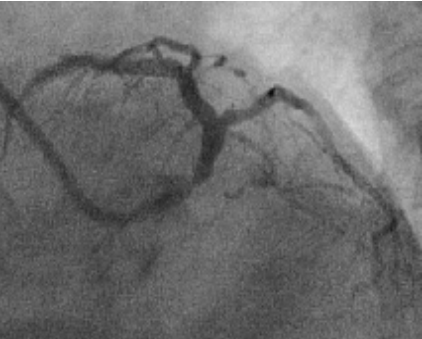

Six weeks after PCI, this patient presented with progressively worsening angina over a two-week period. A repeat angiogram was performed, in anticipation of significant restenosis and it showed an unexpected result, revealing critical disease in ostial left main and patent stents (Figures 2 and 3). Urgent CABG was recommended, but patient refused to undergo surgery. Risks of PCI to left main coronary artery were explained in detail. A 7 French JL 4 guide catheter was selected and guide wire was advanced into distal LAD. Left main lesion was predilated with a 3x13 mm Nimbus Salvo balloon (Clear Stream Technologies Ltd. Wexford, Ireland) and a 4x16 mm (BMS) Clear flex (Clear Stream Technologies Ltd. Wexford, Ireland) was deployed in proximal left main at 18 ATM and post dilated with a 4.5x18 mm Power Sail complaint balloon (Guidant, corporation, Santa Clara USA). End result was successful with TIMI 3 flow distally without any complications. The patient incurred no complications following the procedure.

Figure 2: Antero-posterior cranial view showing critical disease in body of left main coronary artery (Case 1).